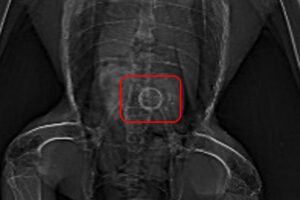

センターに到着して、触診を行いましたが特に大きな骨折などは見られずレントゲンを撮ってみました。

すると、お腹の中におかしな影が見られました。

何か丸いリングのようなものを飲み込んでいるようです。

これが原因で調子が悪いのかもしれません。